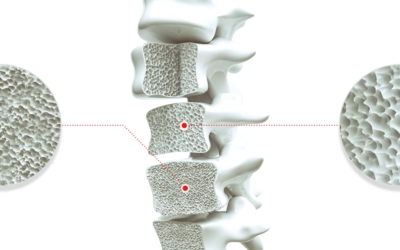

특별히 고령일수록 뼈 건강을 보호해주는 불포화 지방산을 섭취하는것을 통해 골다공증을 방지할수 있어 좋습니다. 국내 연구를 따르면 불포화지방산 섭취에 따른 50대 이상의 여성 골다공증 발병비율을 확인하니 불포화지방산을 복용한 실험군의 발병비율이 약 20% 저감되었다고 발표했습니다. 여러분의 식단에 등푸른 생선등등의 불포화 지방산이 많은 음식을 추가해서 뼈건강을 지켜실수 있도록 해보세요.

콩에는 칼슘과 이소플라본이라 하는 단백질 물질이 다양하게 포함되어 있는데요 이소플라본 물질이 뼈를 만들어 주는 세포를 강화시켜서 골밀도를 높여주며 뼈에서 칼슘이 빠져나가게 하는 파골세포 활성을 억제하는 효과가 있습니다 그리고 여성호르몬인 에스트로겐과 비슷한 역할을 하기 때문에 갱년기의 여성들에게는 좋은 음식이라고 볼 수 있어요.

또한 콩에 함유되어있는 칼슘은 뼈에 흡수가 잘 되기 때문에 골다공증 예방에 좋습니다 두부는 콩보다 칼슘을 빨리 흡수한는 것으로 알려져 있다고 하며 뼈가 약해지지 않도록 골밀도를 높여주는데 큰 장점이 있답니다.